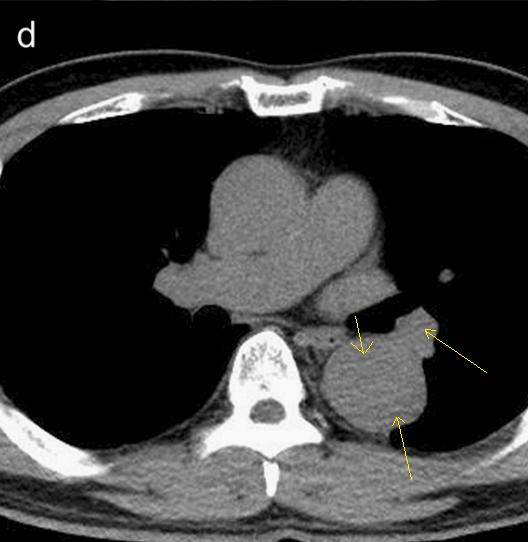

下面这个CT平扫,似乎有大问题!

什么问题?似乎这里有大问题!

图23

同学,你眼神太好使了!

很可惜,这个不是问题,很多CT平扫都有这种线样阴影!

做个增强CT一看,哇,同学,你不光眼神好,运气也不是一般的好!